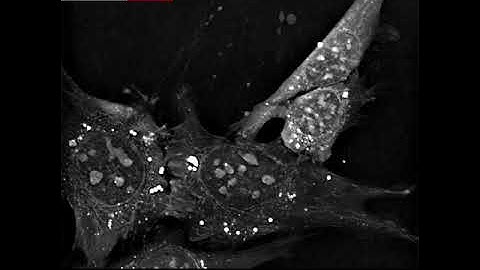

Label-Free Cell Counting for Proliferation Studies | Live-Cell Imaging Explained